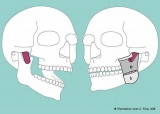

04.04.2022 | Anatomía / University of Basel

Sorpresa anatómica: descubrieron una tercera y súper profunda capa del músculo masetero

Lo novedosos de este hallazgo científico es que nunca se había identificado correctamente ese sector. Pero un reciente estudio de la Universidad de Basilea publicado en Annals of Anatomy reveló la existencia de esta nueva sección, que va desde la apófisis cigomática hasta la coronoides.